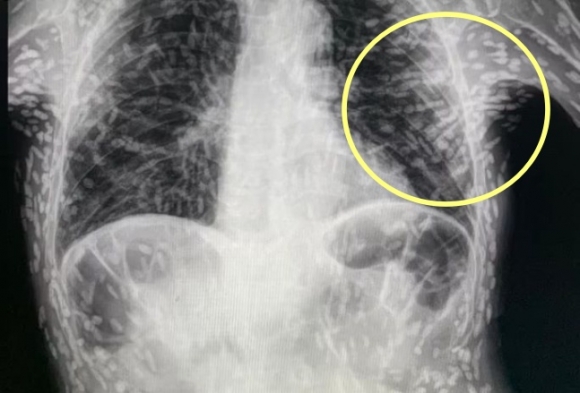

엑스레이를 찍어보니, 온몸에 촌충 같은 기생충이 퍼져있는 것이 Xray사진에 찍혔다.

기침으로 인한 고통을 호소한 환자를 진료하던 의료진은 환자의 엑스레이 사진을 보고 경악했습니다. 엑스레이 촬영물에는 여러 마리의 촌충과 유충이 가득 찍혀있는 것이었습니다.

브라질의 한 의료진이 소셜네트워크서비스(SNS)에 기생충에 감염된 엑스레이 사진을 공개했습니다. 사진에는 몸속에 있는 기생충이 죽어 석회화된 수백 개의 점 형상이 보였습니다.

특히 유충이 근육이나 뇌 조직에 침투한 모습은 매우 충격적이었습니다. 이러한 증상은 유구조충의 유충에 의한 인체감염증으로, 유구 낭미충증이라고도 불립니다.

유구낭미충증은 주로 인간의 장에 사는 촌충의 유충이 근육이나 뇌로 침투할 때 발생합니다. 이 유충은 근육과 뇌에서 낭종과 같은 결절을 형성하기도 합니다.

의료진은 해당 환자가 특별한 치료를 받지 않았다고 밝혔습니다. 그는 "머리, 척수, 눈에 이상이 없는 한 치료가 필요하지 않습니다"라며 "해당 물체들은 석회화되어 있어 생존 가능한 유충이 아닙니다. 불편함을 느끼지 않는다면 특별한 조치가 필요하지 않습니다"라고 말했습니다. 그러나 해당 환자의 뇌에 낭종이 있는지 확인하기 위해 MRI 검사를 기다리고 있다고 전했습니다.